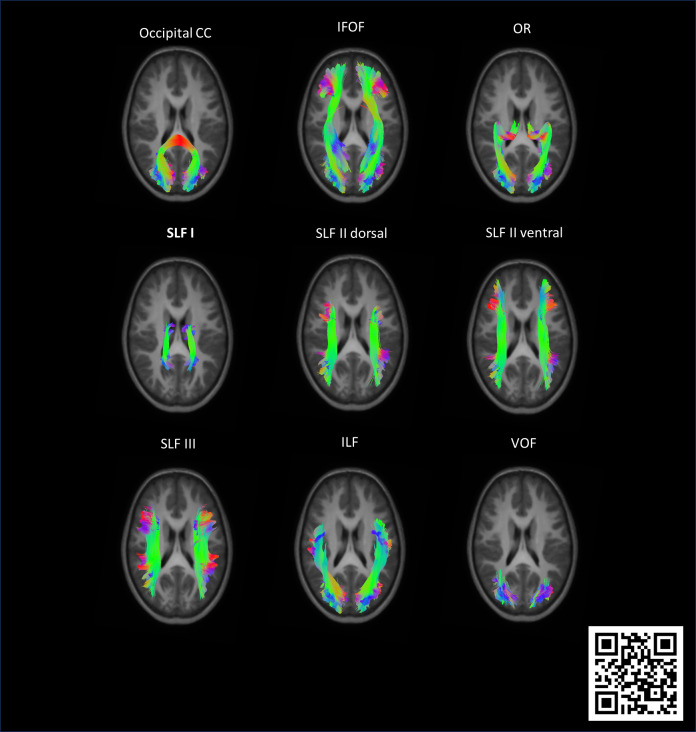

单侧脑瘫(uCP)患儿表现为脑损伤,主要是一侧脑半球,以及白质(WM)病变,已知会影响视觉功能。然而,WM束损伤与视觉结果之间的关系尚不清楚。此外,没有先前的研究全面调查了左、右侧uCP儿童WM视觉通路的半球特异性差异。因此,本探索性研究旨在利用扩散MRI (dMRI)的固定位分析,探讨左右侧uCP儿童视觉通路的微观和宏观结构特征的差异及其与视觉结果的关系。分析36例uCP患儿(7-15岁,男性9例,左侧17例,早产儿15例)的dMRI数据和视觉评估,包括视力和立体视力(即膝蓝纹状体功能)、无运动视觉、视觉运动整合和功能性视觉。计算与视觉功能相关的17个WM束的表观纤维密度(AFD)、纤维束截面(FC)和纤维密度与截面(FDC)。以年龄和颅内容积为协变量,采用Mann-Whitney u检验(r)对AFD和单因素协方差分析(ANCOVA) (ηp 2)对FC和FDC进行差异分析。使用(半偏)Spearman秩相关(rs)研究视觉结果与视束WM特性之间的相关性。左侧uCP患儿的右上纵束、额枕下束和视光辐射的固定指标明显降低。右侧uCP患儿仅在左侧上纵束有较低的AFD、FC和FDC。膝下纹状体视觉功能降低和功能性视觉损伤加重与纤维密度(AFD)降低、束大小(FC)减少以及多个WM束的组合(FDC)有关。低纤维密度(AFD)对无运动视觉感知和视觉运动整合的影响更大。虽然主要的分析是探索性的,没有对多重比较进行校正,但为了透明度,我们还进行了错误发现率(FDR)校正:左、右侧uCP儿童的FC和FDC的几个差异,以及AFD和视觉功能之间的相关性仍然很显著,并在补充材料中报道。总之,我们的探索性研究强调,基于固定体的分析可以进一步了解uCP儿童视觉系统的半球差异以及视觉功能与脑损伤之间的复杂关系。基于我们的研究结果,未来的研究可以完善回归模型,以针对与视觉结果相关的关键WM束,识别潜在的生物标志物来预测视觉障碍,并为uCP儿童提供早期定制支持。

Children with unilateral cerebral palsy (uCP) present with brain damage, predominantly lateralized to one hemisphere, and white matter (WM) lesions, which are known to affect visual functions. However, the relation between WM tract damage and visual outcomes remains unclear. Additionally, no prior study comprehensively investigated hemispheric-specific differences in WM visual pathways between children with left- and right-sided uCP. Therefore, this exploratory study aims to investigate differences in micro- and macrostructural properties of the visual pathways between children with left- and right-sided uCP and their relation to visual outcomes, using fixel-based analysis of diffusion MRI (dMRI). dMRI data and visual assessments, including visual acuity and stereoacuity (i.e., geniculostriate functions), motor-free visual perception, visuomotor integration, and functional vision, were analysed in 36 children with uCP (aged 7-15, 9 males, 17 left-sided, 15 preterm). Apparent fiber density (AFD), fiber-bundle cross-section (FC), and combined fiber density and cross-section (FDC) were calculated for 17 WM tracts related to visual functions. Differences between children with left- and right-sided uCP were investigated using the Mann-Whitney U-test (r) on the AFD and one-way analysis of covariance (ANCOVA) (ηp 2 ) on the FC and FDC, with age and intracranial volume as covariates. Correlations between visual outcomes and WM properties of the visual tracts were studied using (semi-partial) Spearman Rank correlations (rs ). Children with left-sided uCP showed significantly lower fixel metrics in the right superior longitudinal fasciculus, inferior fronto-occipital fasciculus, and optic radiation. Children with right-sided uCP had lower AFD, FC, and FDC in the left superior longitudinal fasciculus only. Reduced geniculostriate visual functions and more impairments in functional vision were associated with lower fiber density (AFD), reduction in bundle size (FC), and their combination (FDC) of several WM tracts. Lower performance on motor-free visual perception and visuomotor integration showed more associations with lower fiber density (AFD). While the primary analyses were exploratory and uncorrected for multiple comparison, false discovery rate (FDR) correction was additionally performed for transparency: several differences in FC and FDC between children with left- and right-sided uCP, and correlations between AFD and visual function, remained significant and are reported in the Supplementary Materials. In conclusion, our exploratory study highlights that fixel-based analysis can provide further insights into hemispheric differences in the visual system and the complex relations between visual functions and brain damage in children with uCP. Based on our results, future studies could refine regression models to target key WM tracts linked to visual outcomes, identifying potential biomarkers to predict visual impairments and enable early tailored support in children with uCP.